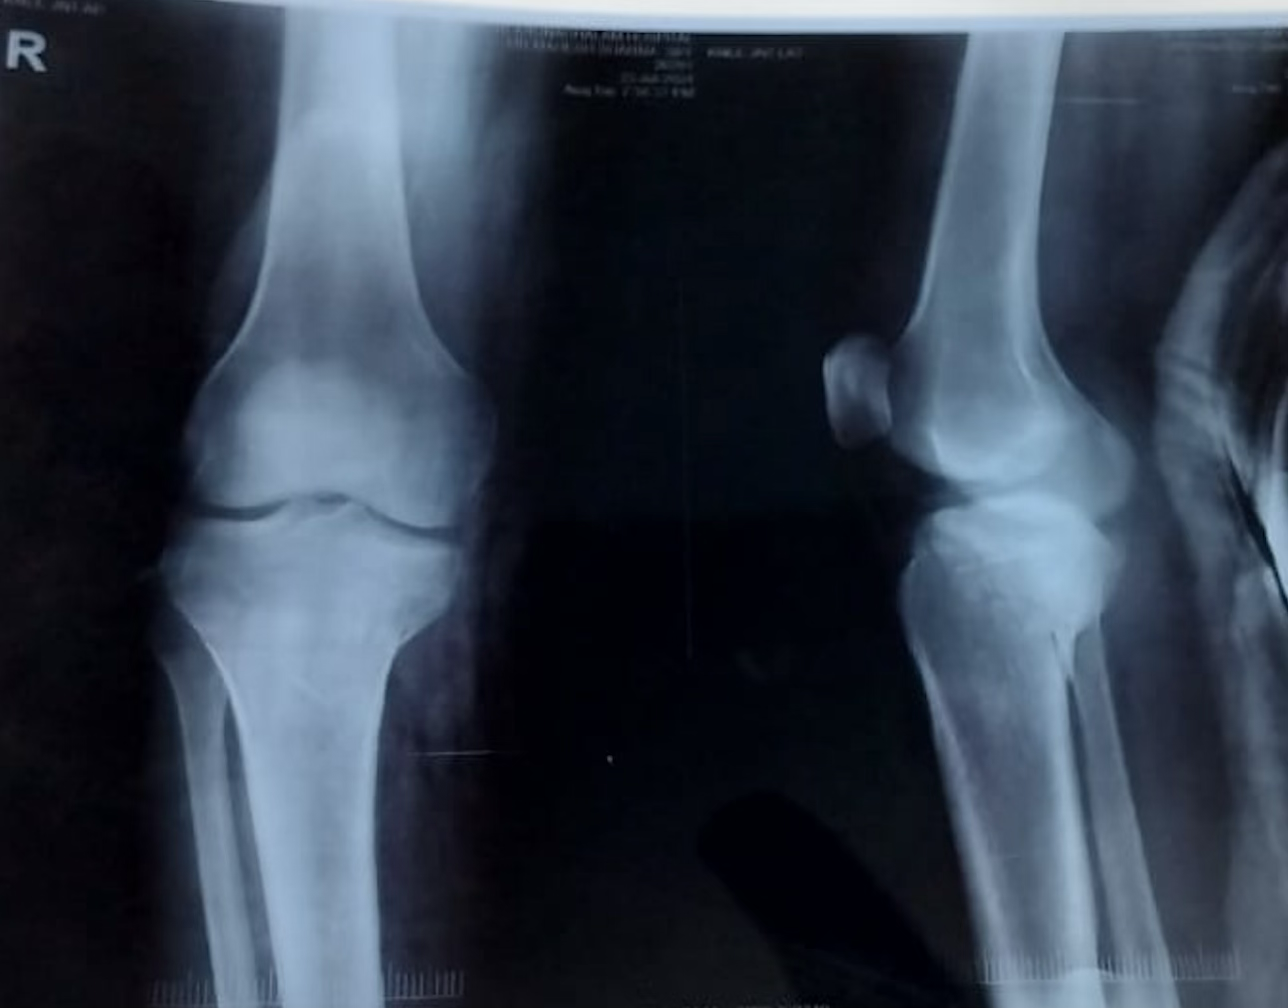

A 35-year-old female presented to the orthopedic outpatient department with a 3-year history of persistent anterior knee swelling and pain affecting her right knee. She denied any major inciting trauma, although she recalled a minor fall in adolescence, which she believed was unrelated. Over time, the swelling gradually increased in size, and her discomfort worsened with knee flexion or prolonged weight bearing. She had no constitutional symptoms such as fever, weight loss, or malaise. Her past medical history was unremarkable, and there was no significant family history of vascular malformations. On examination, the patient lay supine with neutral alignment of the lower limbs. A palpable swelling measuring approximately 5 cm × 4 cm was observed in the infrapatellar region just medial to the patellar tendon. There were no signs of skin discoloration, venous prominence, or sinus formation. Palpation elicited mild tenderness; however, there was no local rise in temperature. Knee flexion was possible from 0° to 130° with discomfort at the terminal arc, exacerbated by deep flexion. Initial plain radiographs showed a non-specific soft-tissue prominence in the same area without evidence of bony involvement or calcifications. An MRI of the right knee revealed a lobulated lesion in Hoffa’s fat pad measuring about 4.8 cm × 2.6 cm × 4.9 cm, hyperintense on T2-weighted sequences and displaying septations consistent with vascular channels. No extension into bone or joint cartilage was evident, and there were no features suggesting aggressive infiltration. Based on these findings, a vascular malformation-likely a cavernous hemangioma-was suspected. The patient was counseled regarding the need for surgical excision to alleviate symptoms and confirm the diagnosis. After pre-operative clearance and standard laboratory work-up, she underwent surgery under spinal anesthesia with a pneumatic tourniquet applied to the thigh. An anteromedial longitudinal incision was made over the infrapatellar area. Careful dissection revealed a well-defined vascular mass within Hoffa’s fat pad. En bloc resection was performed, ensuring clear margins. Hemostasis was secured, and the wound was closed in layers with a drain in place (Figs. 1, 2).

Figure 1: Plain radiograph of right knee antero-posterior and lateral view shows no bone lesion.